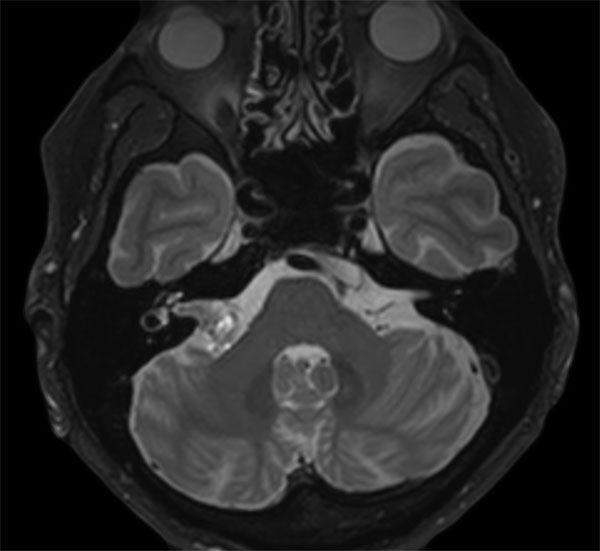

IAC – Acoustic Neuroma

Decreasing hearing of the right side. Buzzing and beating sensation in the right ear. Sometimes pain. Request for MRI of the inner ear without and with contrast agent.